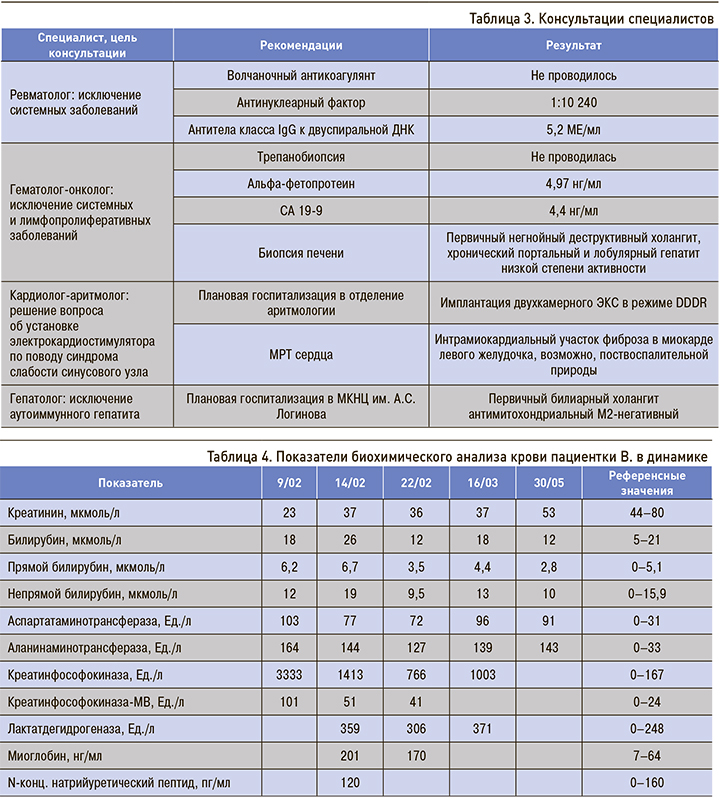

Заключения специалистов с рекомендациями представлены в таблице 3.

После лечения ингибиторами АПФ (периндоприл в дозе 5 мг), бета-адреноблокаторами (пропранолол по 40 мг), спиронолактоном по 50 мг, НПВП (диклофенак раствор 2,5%, 3 мл) состояние пациентки улучшилось: уменьшилась выраженность одышки и пастозность голеней. Лабораторные показатели в динамике представлены в таблице 4.

В связи с улучшением клинического состояния пациентка выписана под наблюдение терапевта и кардиолога по месту жительства. 24.04.2018 после консультации врача-аритмолога в плановом порядке по показаниям имплантирован электрокардиостимулятор (ЭКС).

Результаты комплексного лабораторного и инструментального обследования с биопсией печени подтвердили наличие первичного билиарного негнойного деструктивного холангита, хронического портального и лобулярного гепатита низкой степени активности.